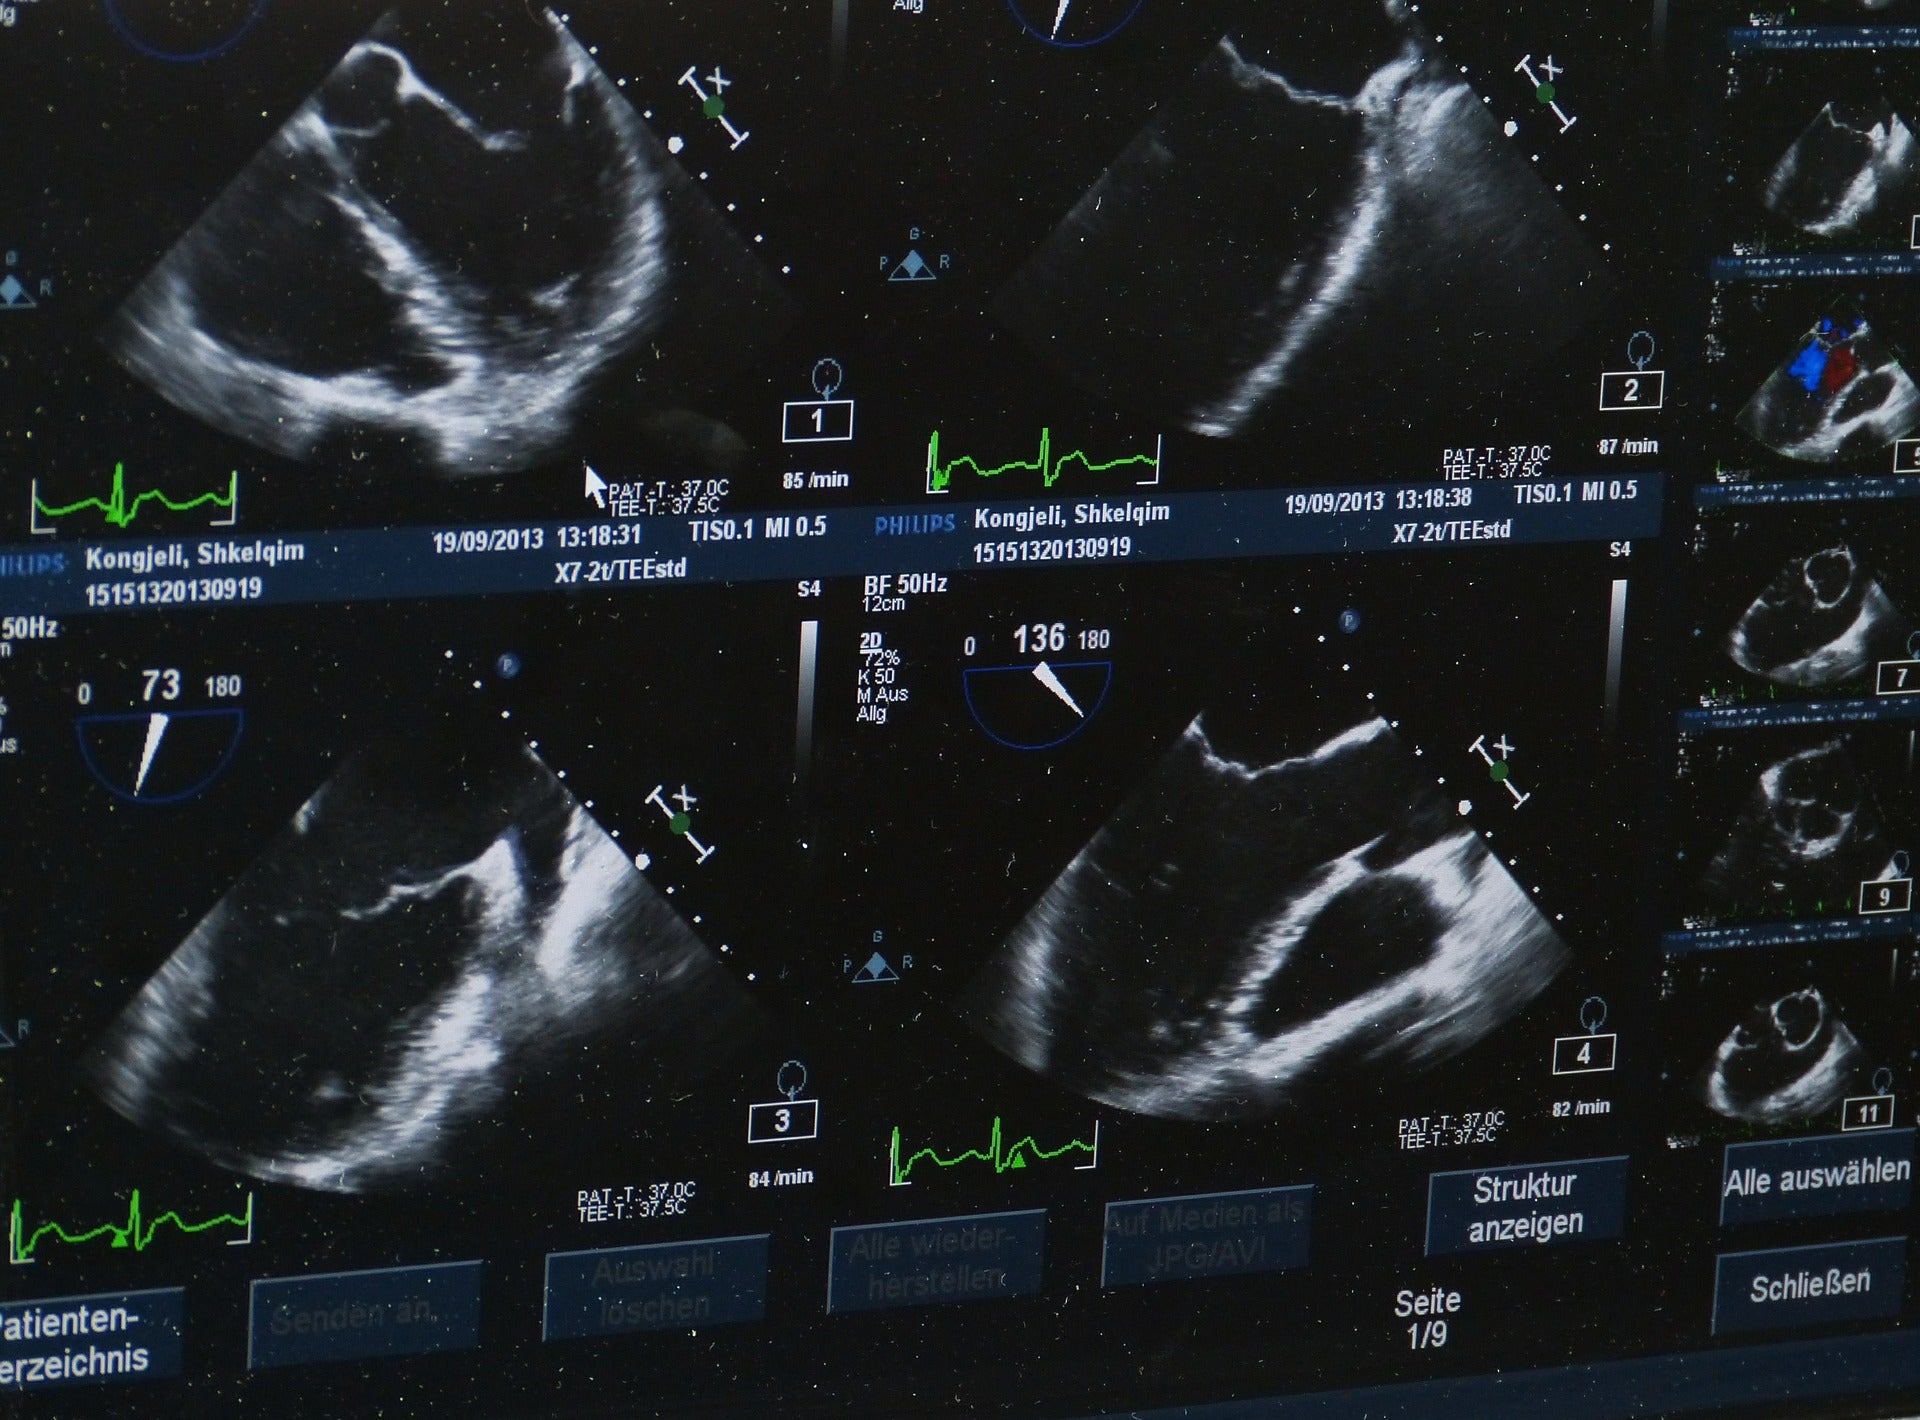

We talk with our physical therapy guests about what medical imaging can and can’t do when it comes to identifying sources of pain in your body. We also talk about why it can be so difficult to determine the source of the problem when it comes to the hips, glutes, groin and lower back.